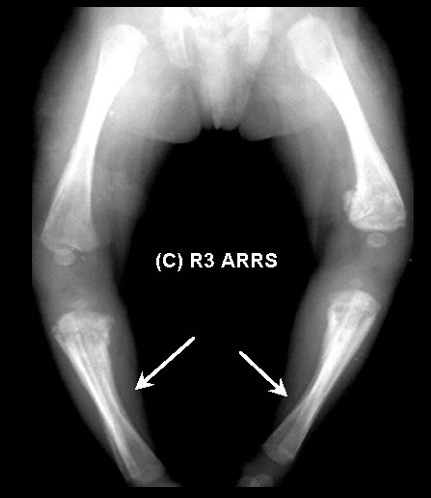

Saber shins: Anterior bowing of tibia

Saber shins: